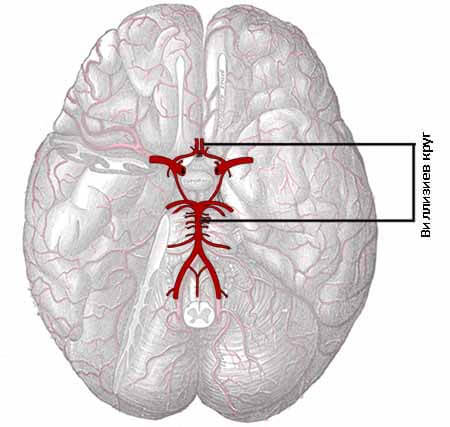

Анатомия: Задняя соединительная артерия мозга

Раздел: Фотоэссе